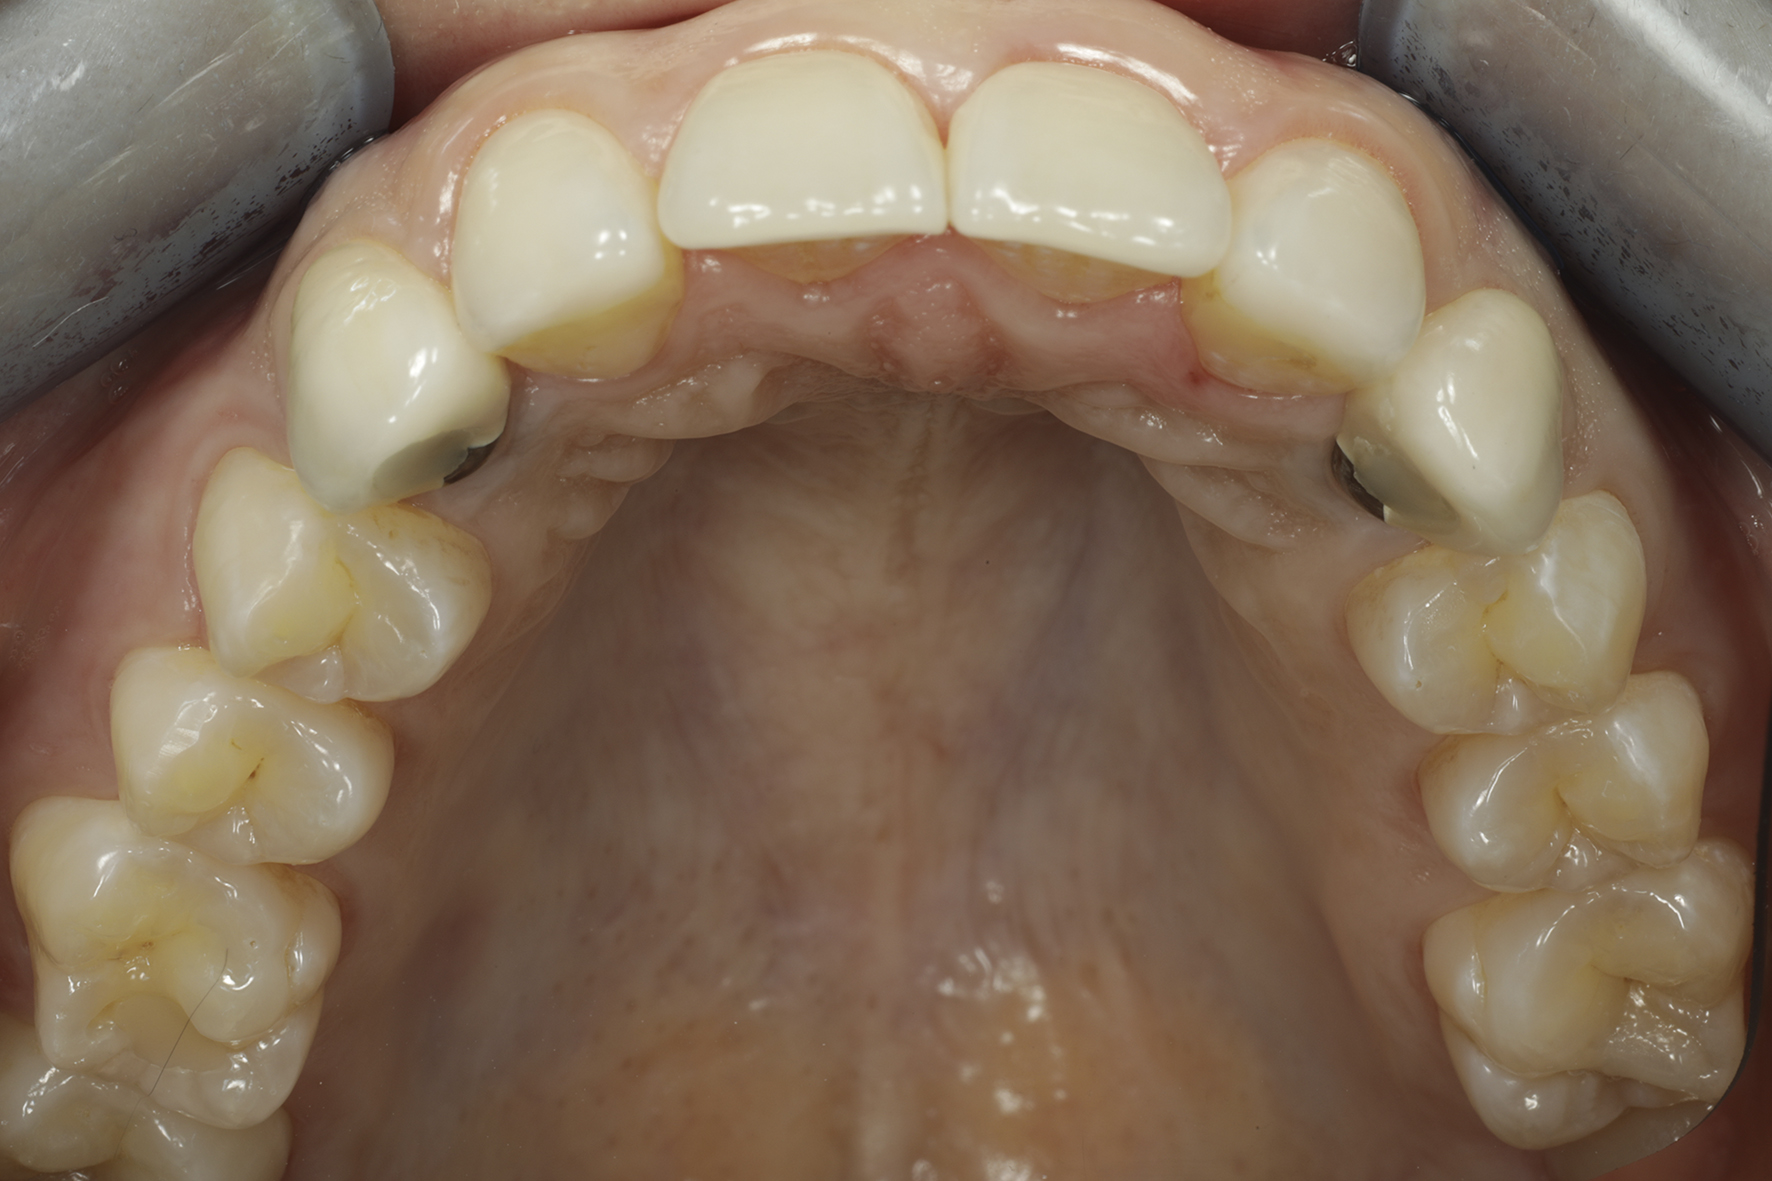

Lopputilanne 1/4. Implanttikruunut kulmahampaissa sekä ohuet keraamiset kuoret neljässä yläetuhampaassa paikoillaan.

Lopputilanne 2/4

Lopputilanne 3/4

Lopputilanne 4/4